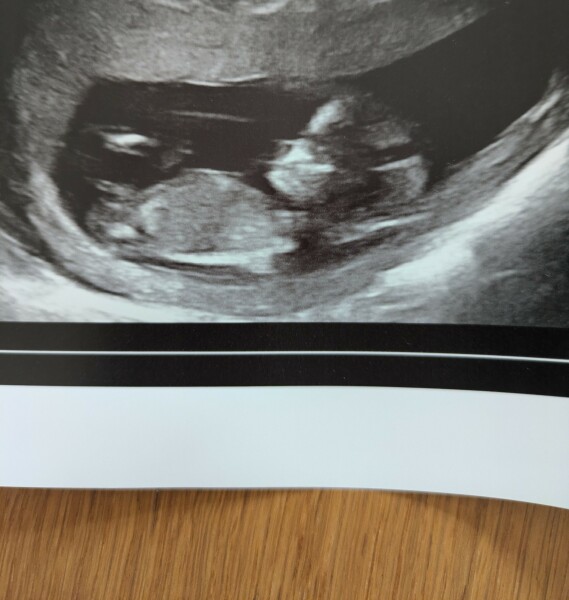

Ontheflipside_ · 08/07/2024 18:59

Hi ladies, hope everyone is doing well. I

We had our dating scan today, due 18th Jan

3dpo

Awww adorable. Baby looks so perfect and snug. I'm glad it's going well! How you feeling?